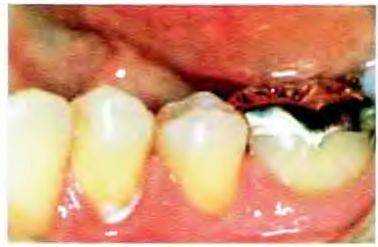

Рис. 12-48. Второй моляр нижней челюсти препарирован под МОД-накладку. Дистальный корень первого моляра удалось сохранить после эндодонтического лечения и гемисекции зуба Корень предполагается использовать в качестве опоры мостовидного протеза. Медиальный корень удален по пародонтологическим показа-

Рис. 12-49. Окклюзионный вид гипсовой модели Хорошо видны детали культи зуба, препарированного под МОД-накладку.

Рис. 12-50. Внешний вид готовой МОД-накладки на втором моляре нижней челюсти. Мостовидный протез с опорой на дистальный корень первого моляра.